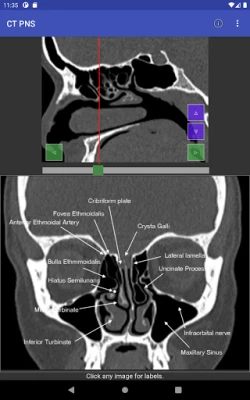

Domin sauƙaƙa fahimtar tsarin jikin ɗan adam ta hanyar hotunan CT scan, mun haɗa abubuwan ciki a matakai biyu (planes). Ɗaya daga ciki yana aiki a matsayin jagora (reference) wanda zai taimaka wajen fahimtar ɗayan sosai. Wannan hanya tana sa fahimtar tsarin jikin ya zama mai sauƙi da inganci, kamar yadda ake fuskanta a yanayin asibiti na gaskiya. Bugu da ƙari, za a iya gungurawa (scrolled) kowane mataki daban-daban, wanda hakan ke ba da damar fahimtar zurfin kowane sashi da cikakkun bayanansa cikin sauƙi.